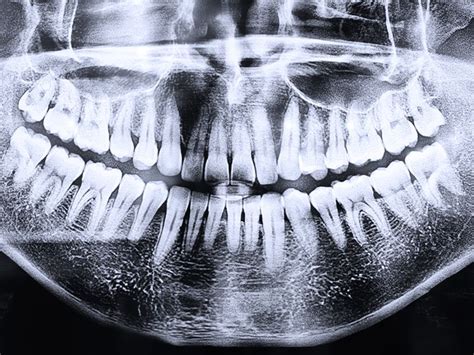

El diente de leche hace las funciones de guía del permanente, marcando el camino por donde debe salir. Si el de leche se cae antes de tiempo, el definitivo pierde la guía para hacer erupción. En caso de que esto ocurra, es posible encontrar la ubicación del diente mediante una radiografía y entonces hacer el tratamiento adecuado. Otra causa puede ser un traumatismo en los dientes de leche, que terminan empujando el definitivo hacia el hueso.

La extracción de los dientes de leche es una solución cuando el diente no se cae cuando debería, impidiendo que el diente permanente erupcione. Esto se realiza cuando el diente de leche está muy adherido, es decir, no se mueve con facilidad. También puede ser una solución si con rayos X se nota que el diente permanente está formado completamente debajo de la encía.

Cuando ocurre alguno de estos problemas, la pregunta frecuente es cómo bajar un diente retenido. Lo primero que hace el dentista es una evaluación física de la boca del niño, normalmente se hacen radiografías para un diagnóstico completo. En el caso de la agenesia, las piezas dentales nuevas no se forman, por lo tanto, la solución pasa por colocar implantes. Mientras que en el resto de los casos, el odontólogo estudiará cuál es la mejor solución. Por ejemplo, si el problema es la encía se puede abrir un poco para abrirle camino al diente nuevo. En otros casos se recurre a la ortodoncia.